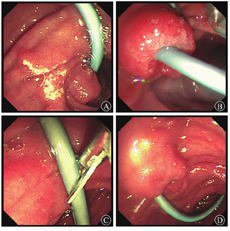

2019年1月30日行内镜下鼻胆外引流管变更内引流支架术(图2)。术后患者食欲改善,2周内体质量增加5 kg。2月11日患者出现发热,体温为37.7 ℃,上腹部疼痛,伴后背放射痛。查血常规未见异常,血生物化学检查示AST水平为88.2 U/L,胆红素水平在正常范围内,血淀粉酶水平为174.1 U/L(正常参考值为0~150.0 U/L ),血脂肪酶水平为352.7 U/L(正常参考值为13.0~60.0 U/L),不排除因乳头占位压迫胰管可能,予禁食水、对症支持治疗。2月13日行十二指肠乳头肿物内镜下切除术+超长胆胰管支架转流(鼻胆外引流管改造)术。术中先行超声内镜检查,初步评估乳头部占位无明显胆管、胰管内生性生长,但胰管扩张明显(图3)。考虑乳头病变浸润相对较深,为避免肿瘤组织残留或复发,切除乳头病变时尽量深切,术后创面可见固有肌层显露。为避免胰液或胆汁刺激创面而引起迟发出血或穿孔,术中置入鼻胆外引流管改造的超长(约35 cm)胆胰管支架转流,将胰液和胆汁跨过乳头切除创面引流至远端空肠,创面予金属夹夹闭(图4)。术后病理结果(图5)提示十二指肠乳头壶腹部低分化腺癌,癌旁和表浅腺体呈管状-绒毛状腺瘤改变,癌灶大小约1.5 cm×1.0 cm×0.5 cm,癌组织侵犯十二指肠肠壁肌层,紧邻基底切缘(切缘电凝变性显著)。术后当天和第2天胃管内共引流出约220 mL血性液体,发热,体温最高38.5 ℃,右上腹疼痛,查体无腹膜刺激征。复查血红蛋白较前无明显下降,白细胞计数为9.17×109/L,中性粒细胞占比为0.81,IL-6水平为80.4 ng/L,血淀粉酶水平为183.3 U/L,血脂肪酶水平为292.26 U/L,余未见明显异常。予以禁食水、抗感染(静脉注射亚胺培南西司他丁钠,1 g/8 h)、止血(经静脉泵注射艾司奥美拉唑、生长抑素,静脉注射酚磺乙胺、卡洛磺钠,口服凝血酶冻干粉等)、静脉营养支持等治疗。患者胃管内出血逐渐停止,腹痛渐缓解,1周后拔除胃管,逐步恢复饮食。患者于2019年5月31日至解放军总医院第一医学中心复查,十二指肠检查结果未见异常,活组织病理学检查示慢性炎,正电子发射计算机断层显像(PET-CT)检查未见明确肿瘤残留、复发或远处移位。2019年10月外院复查腹部增强CT亦未见明显异常。遂继续随访观察至今,患者无明显不适。

消化内科王子恺副主任医师:患者为老年男性,以腹痛起病,外院初诊为"胆总管结石",遂行ERCP术治疗。术中胆管造影未见结石,置入鼻胆引流管外引流。发现十二指肠乳头肿大,病理活组织检查示腺瘤样改变伴轻、中度异型增生。为改善患者营养状态和提高生命质量,解放军总医院第一医学中心消化内科先将鼻胆引流管由外引流改为内引流,待患者一般状况好转后行超声内镜评估,排除乳头占位胆胰管内生性生长后,行十二指肠乳头肿物内镜下切除术。术中为预防术后复发、残留,乳头病变予深切至固有肌层。术后为减少胆汁、胰液对局部创面的化学性刺激,预防出血、穿孔、胰腺炎和胆管炎,置入7 F鼻胆外引流管改造胆胰管支架,头端甩向空肠,并置入胃管。切除标本予多刀切片,病理示十二指肠乳头壶腹部低分化腺癌,癌旁和表浅腺体呈管状-绒毛状腺瘤改变,癌组织侵犯十二指肠肠壁肌层,紧邻基底切缘。十二指肠乳头病变的治疗模式是选择外科手术还是内镜切除,以及内镜切除的适应证和内镜切除术后并发症预防措施都是本次讨论的重点,还需请肝胆外科和病理科专家参与,结合本病例的病理结果制定进一步治疗方案,明确该患者后续治疗。

近1年内,解放军总医院第一医学中心消化内科曾收治2例内镜下切除术后穿孔、继发严重腹膜后感染的患者,为避免胆汁和胰液对乳头部创面的化学性刺激,在内镜下切除术后均予放置胆管和胰管塑料支架。其中1例患者穿孔位置为乳头部肛侧,由于胆管和胰管支架长度较短,非但不能避开穿孔部位,反而将胆汁和胰液直接引流至穿孔部位,引起持续化学性刺激而加重穿孔和腹膜后感染。为解决这个棘手问题,李闻主任将鼻胆引流管改造成超长胆管、胰管内引流支架,可跨过穿孔部位,配合经皮腹膜后穿刺置管引流和内镜清创腹膜后感染坏死组织,该患者最终康复出院,但住院时间长,费用高,患者痛苦极大。在本例患者的内镜下切除术中,李闻主任在患者胆管和胰管内直接放置鼻胆引流管改造的超长支架,将支架远端甩至空肠,最大限度避免了胰胆液对局部创面的刺激,减少了术后并发症的风险,这为内镜下切除术后并发症的预防提供了新思路。